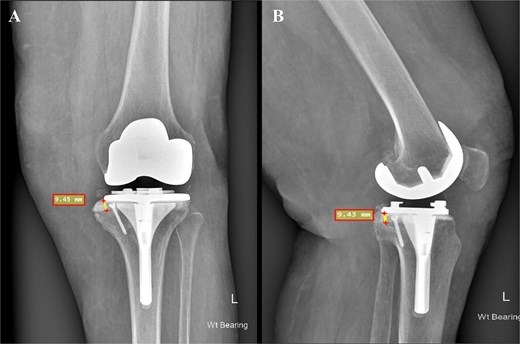

In the present case, the BCSA technique was selected as the most suitable based on the pre-operative plan. The rationale for deeming BCSA the most appropriate option among others included the following: (i) the defect did not exceed 15%–20% of the tibial surface area, (ii) the technique permitted the use of standard primary TKA systems rather than necessitating revision prostheses as with metal augments, (iii) this method would preserve existing bone and soft tissue attachments, thereby facilitating both the planned primary and even a potential revision procedure, and (iv) the patient was obese with a BMI exceeding 30 and a diagnosis of established osteoporosis. Consequently, the use of excessive hardware combined with additional metal augments would elevate the mechanical load and increase the risk of future periprosthetic fracture. Our patient exhibited a bone defect of ~9.45 mm following the final tibial cuts (Fig. 3). Using cement alone in such a defect could have resulted in cement lamination, shrinkage, cracking, and early mechanical failure [17]. In our view, the application of the BCSA technique in this patient allowed for optimal cement pressurization within the defect, enhancing implant stability and fixation. At the 2-year follow-up, the patient showed excellent radiographic results (Fig. 4) and satisfactory clinical recovery (Video 1).

Postoperative face (A) and profile (B) X-rays depicting a medial tibial bone defect ~9.45 mm from the baseplate. The 3.5 mm cancellous screw is indicative of the applied BCSA technique.